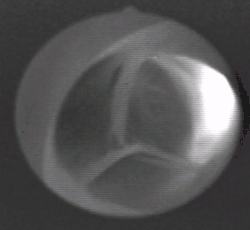

Аорта́льный кла́пан (лат. valva aortae) — один из клапанов сердца человека или других теплокровных животных, располагающийся на границе левого желудочка и аорты, препятствуя обратному току крови из аорты в левый желудочек в диастолу. У человека клапан имеет три створки, открывающихся в сторону аорты. Полулунные створки, смыкаясь, перекрывают отверстие, соединяющее аорту и левый желудочек. Створки крепятся к фиброзному кольцу, которое образует отверстие между аортой и левым желудочком.

- пик открытия створок, приходится на первую фазу максимального изгнания крови: свободные края створок максимально изгибались в сторону синусов, форма открытия клапана приближается к кругу;

- период устойчивого открытия створок, приходится на вторую фазу максимального изгнания крови: свободные края створок выпрямляются вдоль оси потока, клапан принимает форму цилиндра, и створки постепенно прикрываются, форма открытия клапана становится треугольной;